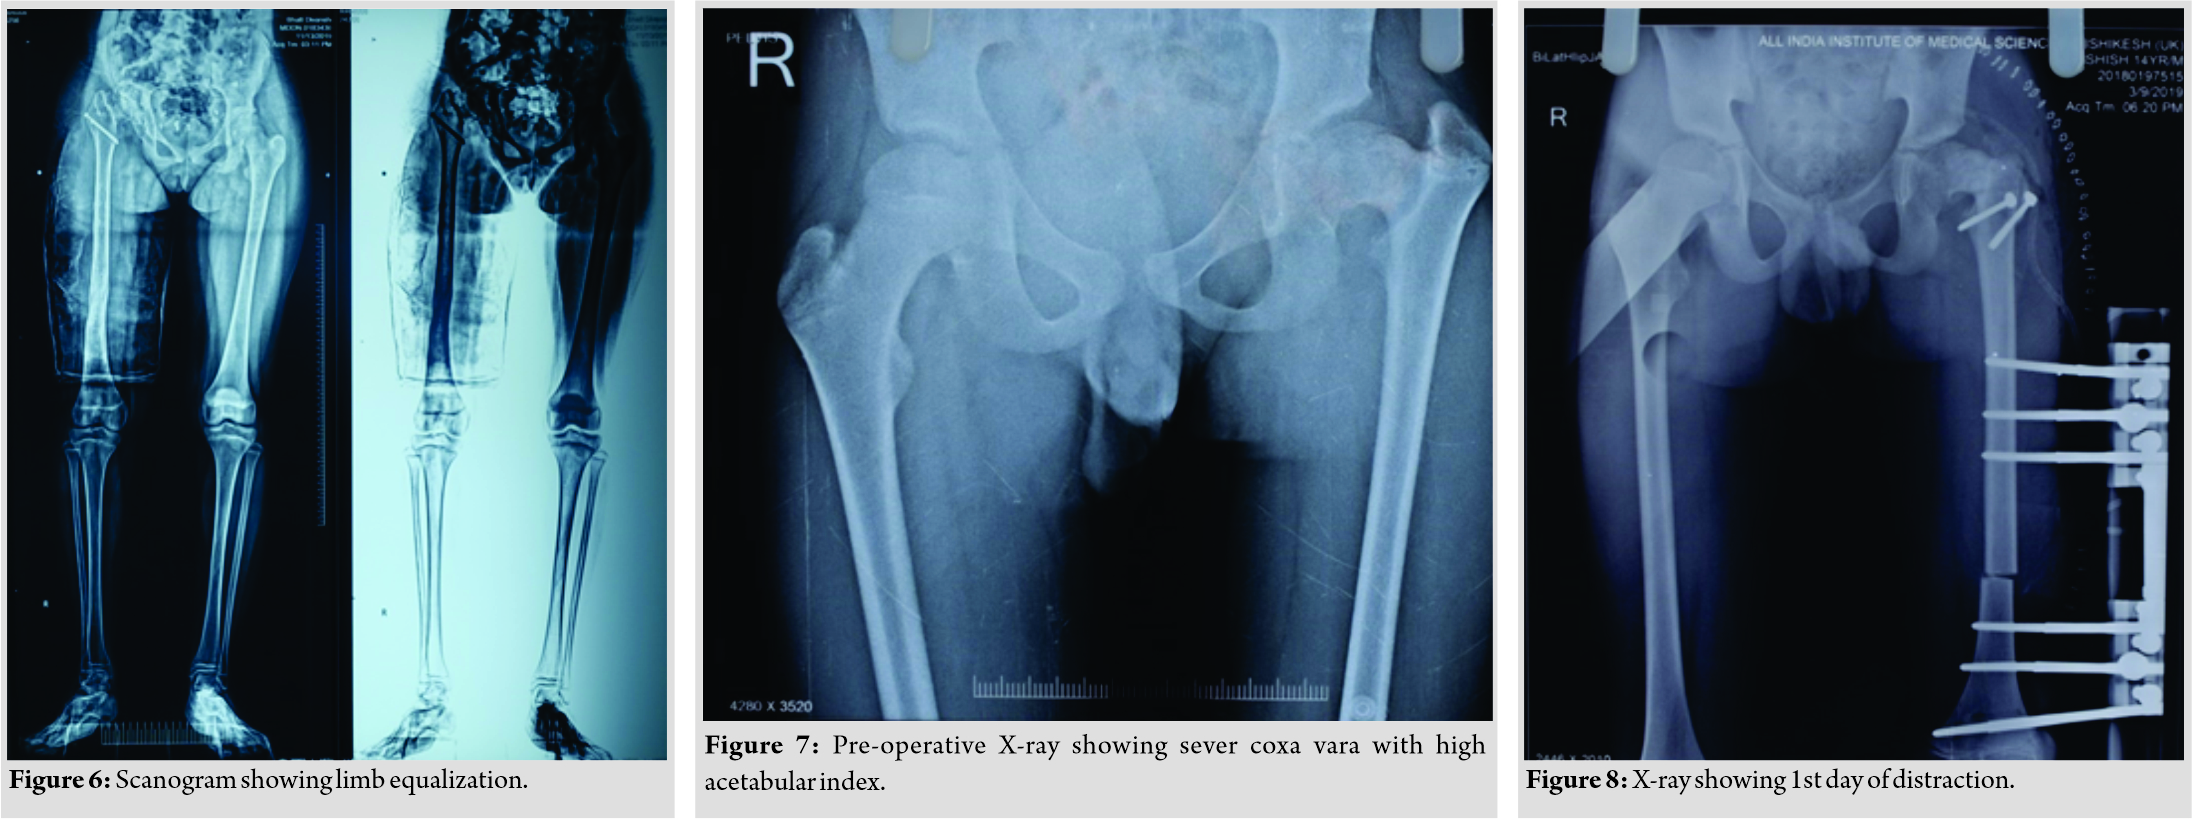

Care was taken to preserve the piriformis attachment on to main femoral fragment. With the help of patella holding clamp, the GT fragment was held and shifted to 2 cm distally and fixed with two 4 mm cannulated cancellous screws. The wound was closed over the suction drain and the patient was then planned for monorail external fixator in the supine position. Gradual distraction was started from the 5th post-operative day (Fig. 3).  Careful follow-up evaluation was done and distraction was stopped once limb length equalization was achieved (Fig. 4-6). The fixator was removed after 112 days. The patient had no complication postoperatively except mild pain during early phases of distraction which was managed with high-dose analgesics and knee stiffness in the later part of the distraction. She achieved a complete range of motion of knee with extensive physiotherapy and quadriceps strengthening exercises. At final follow-up of 6 months, the patient had no equinus at the ankle with improvement in hip abduction with minimal abductor lurch.

Careful follow-up evaluation was done and distraction was stopped once limb length equalization was achieved (Fig. 4-6). The fixator was removed after 112 days. The patient had no complication postoperatively except mild pain during early phases of distraction which was managed with high-dose analgesics and knee stiffness in the later part of the distraction. She achieved a complete range of motion of knee with extensive physiotherapy and quadriceps strengthening exercises. At final follow-up of 6 months, the patient had no equinus at the ankle with improvement in hip abduction with minimal abductor lurch.

The second patient, a 14-year-old male, presented to us with complaints of limping in the left lower limb without any pain in the hip joint. He also had a history of septic arthritis in the left hip which was managed non-operatively in a village hospital. There was no history of trauma, weight loss, or tuberculosis. On examination, it was found that the patient had limited terminal hip ROM with severe restriction in hip abduction (25°). There was a true shortening of 6 cm in the left femur and the patient walked with abductor lurch without any ankle equinus with excessive flexion in the opposite knee. An X-ray revealed severe coxa vara on the left side with increased acetabular index (Fig. 7). There was minimal joint space narrowing medially. The femoral diaphysis was thin as compared to the opposite side. The power of the muscles around the hip and knee was comparable to the opposite side. Based on these findings, it was classified as a case of Choi’s Type 2 septic sequelae of the hip with 6 cm of femoral shortening. The patient underwent trochanteric advancement distally as described in the previous case along with a simultaneous application of monorail external fixator and corticotomy in the distal femur. The distraction started on the 5th post-operative day in equal increments of 0.25 mm every 6 hourly (Fig. 8 and 9). After achievement of limb length equalization, the fixator was removed after 114 days. Three weeks after this, the patient presented with a fracture of the regenerate with minimal angulation and was managed further by one and a half spica cast for further 4 weeks (Fig. 10). At latest 12 months follow-up, the patient was walking normally with minimal abductor lurch.